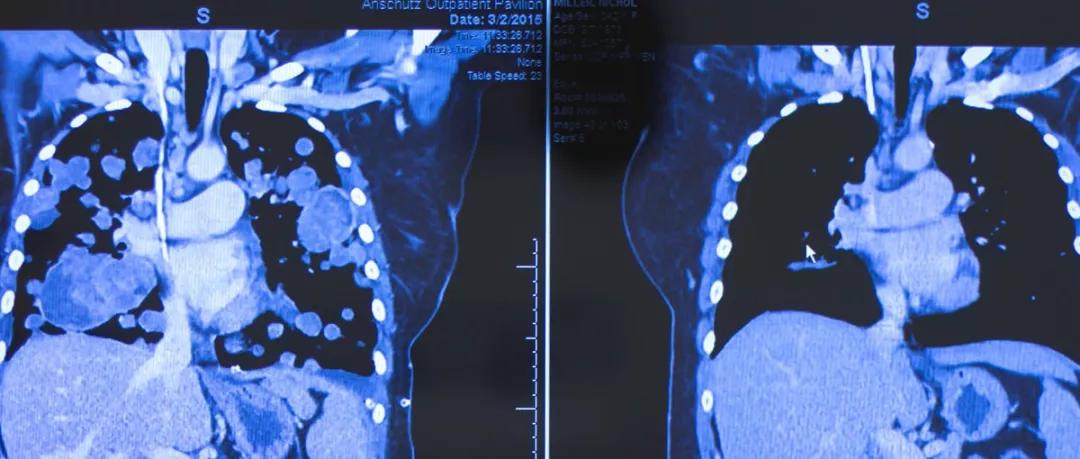

肿瘤充满了90%的肺部,即将死亡的晚期患者,接受抗癌“神药”拉罗替尼治疗后病灶消失殆尽,重获新生。